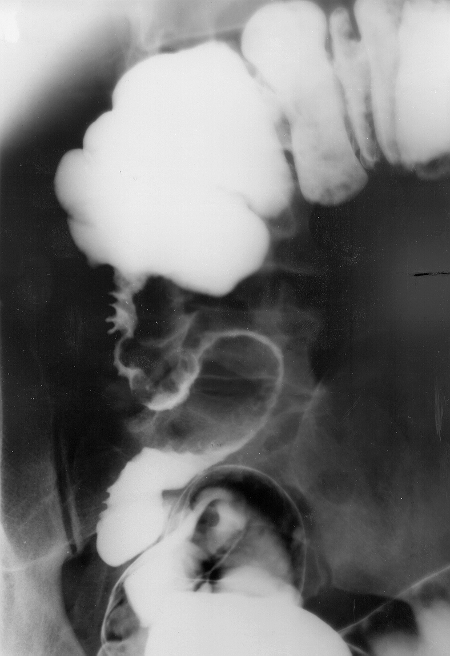

Konvansiyonel Radyoloji

• Kontrastlı grafilerde oral yolla verilen baryumun kontrast ajan olarak kullanılması ile ince barsak pasaj grafileri çekilir.

• Opak maddenin geçiş süresi

• Opak maddenin takılması

• Lümende olabilecek doluş defektleri

• Mukozal yapının daha iyi ortaya konabilmesi amacıyla “enteroclysis”.